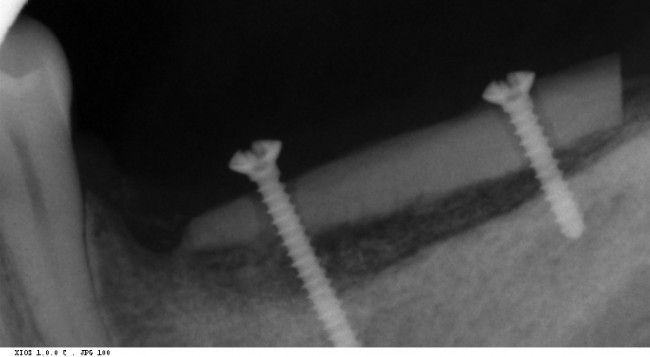

Это можно увидеть по прицельному снимку, который мы сделали через 3 месяца после остеопластики:

Вспомните, как стояли винты сразу после операции и как они выглядят сейчас.

Обратите внимание на появление новообразованной костной ткани под блоком — на снимке наглядно прослеживается ее губчатая структура. Пока границы слоев костной ткани видны хорошо, но, в дальнейшем, они почти исчезнут.